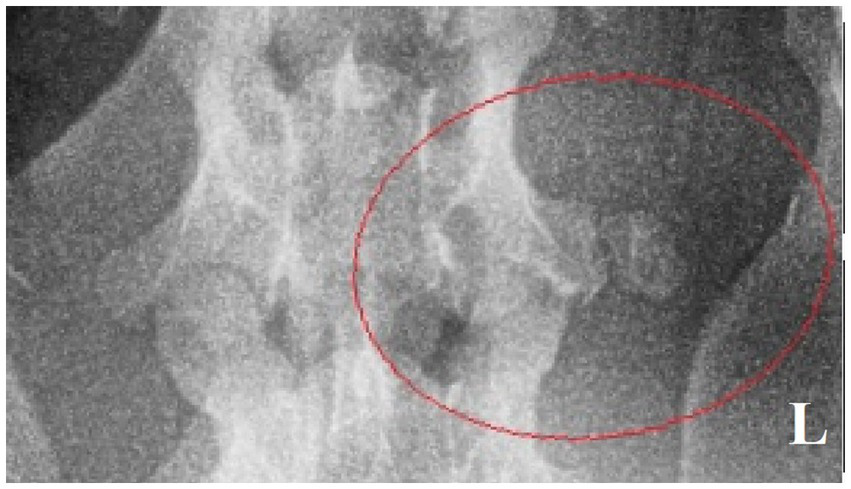

Figure 4

Ventrodorsal radiograph of the cervical region with a small osseous lesion after 2 years from the surgery (red ellipse).

HO within the skeletal muscles is in human medicine typically described as fibrodysplasia ossificans progressiva (genetic form) and myositis ossificans traumatica or circumscripta (acquired form), the mechanism of which is not fully understood and is mostly suspected to be secondary to trauma. In cases of both genetic and acquired forms, a recurrence of lesion after surgical excision is common, as was observed in the described case report 2 years following the surgery. Periodical recheck radiographs were obtained because the residual tissue suggested possible regrowth and a general potential for HO recurrence. Another excision will follow if necessary (20). HO in dogs is rare, with most reported cases affecting hip joints and the appendicular muscles (9, 10, 21, 22). One similar report of HO close to the cervical spine in a dog with lameness was published, but no connection with neural structures was mentioned (8). In the case presented here, the combination of diagnostic imaging and histopathology was consistent with reports of HO in human medicine. A combination of imaging modalities (CT, MRI, and Doppler ultrasound) is used in HO diagnostic procedures in people. In our case, we used a combination of radiographs and MRI, where matured HO presents as a cancellous fat that is hyperintense on T1W and T2W images outlined by the hypointense cortical bone, which can be considered diagnostic. In this case, the HO was diagnosed at a later stage, when trabecular bone had formed. In people (compared to veterinary medicine), radiographic and histologic features of earlier HO stages (which have different characteristics) have also been described. Therefore, when MRI detects a mature HO, no further imaging is necessary. On the other hand, MRI of earlier stages of HO has a great advantage in excluding other differential diagnoses—recognizing MRI patterns in HO could be very beneficial in the early phases as the condition is commonly misdiagnosed for osteomyelitis or malignancies such as sarcomas (23–26). The histologic features mirrored radiographic findings—the early lesion shows very cellular sheets of plump fibroblasts, the cells are spindle-shaped or stellate, and they seem to float in a myxoid extracellular matrix. One week later, seams of osteoid appear in the peripheral portions. In human medicine, because of dense cellularity and osteoid production, lesions at this stage of evolution have been called “pseudomalignant osseous tumors of soft tissue” (27–29). Despite the high cellularity and mitotic figures, cytological atypia and abnormal mitoses are absent. A characteristic feature of HO is the entrapment of skeletal muscle in the peripheral portions of the mass. Six weeks later, the outer portion of the mass shows dense lamellar bone arranged as a pseudocortex. Six months to a year later, lesions evolve into the thick, mature trabecular bone. Bone marrow may also be present in older lesions. Complications of HO can develop as a restriction of movement of adjacent joints, and occasionally a lesion may impinge on an adjacent nerve, a pathology up to this date described only in cats (sciatic and other major nerves were encased in progressive fibrodysplasia ossificans cases) and humans (11, 30). Four factors are theorized as necessary in the pathogenesis of non-genetic HO (31). First, there must be a primary insult, usually an episode of trauma that may form a hematoma. Often, the injury is minimal and consists of only a few torn muscle or collagen fibers. The second factor is a signal from the site of injury—this signal is most probably a protein secreted from cells of the injured tissue or from inflammatory cells arriving in response to the tissue injury. Third, there must be a supply of mesenchymal cells—genes that synthesize osteoid and chondroid material are activated and cause these mesenchymal cells to differentiate into osteoblasts or chondroblasts—HO formation may occur anywhere in these soft tissues, and sites include skeletal muscles and perivascular and fibrous tissues. Finally, a necessary environment that is conducive to the continued production of heterotopic bone must be present. Of these four factors, signaling agents appear to play the most important role in the formation of heterotopic bone, and recent progress has been made in the understanding of these agents in human medicine (4, 32–37). In our case, the owner did not describe any traumatic event, but an injury during the first year of life may be speculated. Although HO may develop spontaneously, the process is initiated by trauma in 60–75% of cases in humans. HO was first described during World War I as a consequence of blast injuries and remains a major cause of morbidity in soldiers returning from conflicts in Iraq and Afghanistan (38–41). A distinctive feature is lesion maturation, which is apparent clinically, radiologically, and histologically. Our patient had episodes of swelling, pain, and signs of inflammation in the history, which is consistent with tissue irritation and HO maturation over several months. A large soft tissue swelling was evident prior to the surgery. The fluid-filled component, with variable tissue characteristics, may represent part of a hematoma, which is described as being seen in the early phases due to hemorrhage (42). HO in human medicine is staged using several classification methods, none of which are used in veterinary medicine. Nevertheless, the paravertebral area is suspicious for post-traumatic HO evolution in our case (43–46). Nerve compression or impingement has been described in stenotic disorders or traumatic events, typically spinal nerves of the lumbosacral region and obturator or sciatic nerves after pelvic fractures or surgeries (47–49). Cases of HO with nerve compression or impingement have not yet been published in dogs in any location along the vertebral column. In the case presented herein, the left C6 spinal nerve was compressed; this nerve is part of suprascapular, subscapular, and musculocutaneous nerves, and consequently, the flexor reflex of the affected thoracic limb is weakened, as was in our patient. The main limitation of the article is the lack of visual direct proof demonstrating nerve entrapment, such as an intraoperative image or sufficient MRI detail to visualize the nerve. Nevertheless, the neurological exam, MRI lesion localization, surgical findings, and resolution of the neurological deficits following surgery are all consistent with the nerve entrapment described in this case. To the authors´ knowledge, this is the first report of HO in paravertebral muscles with nerve impingement or entrapment causing neurogenic lameness in dogs (50).